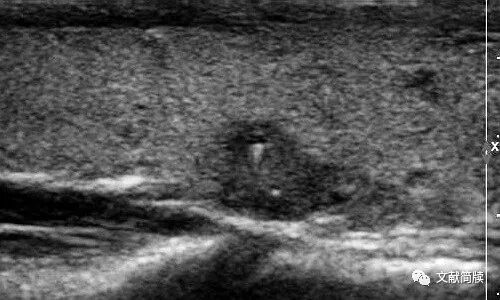

第二,讨论部分,我们认为,乳头状癌结节内部可能存在胶质,超声声像图会表现为结节内部出现的微囊结构(图2)。点状强回声及其后方的彗星尾征,可能是微囊后壁的后方增强效应,或者是平铺于微囊后壁的析出物引起的振铃伪像。这种表现的发生机制主要是因为胶质聚集形成微囊泡,良、恶性肿瘤均可见,并不是恶性肿瘤特有表现。

图2 甲状腺乳头状癌。较大点状强回声前方见小囊(体积较大的微囊),后方见彗星尾征;较小点状强回声前方见微囊,后方无彗星尾征。